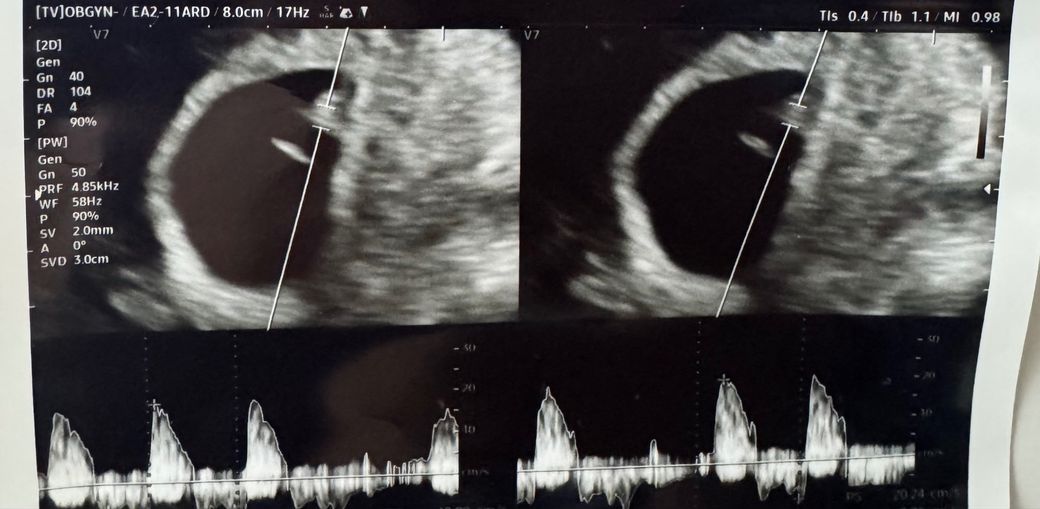

6주 4일차에 심장소리 듣고왔는데 소리가 불규칙적이라고 하네요. 아기 크기는 3mm이고 bpm은 116정도 나옵니다.

일주일 뒤에 다시 보기로 했는데 이런경우 유산가능성이 있다고 하셔서요.아기 심박이 규칙적으로 돌아올 확률이 작을까요?

• 1번 째 사진

• 임신 6주 4일에 태아 길이 3mm, 심박수 약 116회/분이면 수치 자체는 해당 주수에서 정상 범위에 들어갑니다. 이 시기에는 심장이 막 형성되어 전기적 리듬이 아직 불안정할 수 있어, 초음파상 심박이 고르지 않게 들리는 경우가 적지 않습니다. 특히 심박 측정은 짧은 시간의 영상과 각도, 기기 설정에 따라 변동이 커 불규칙처럼 들릴 수 있습니다.

중요한 점은 현 시점의 한 번의 소견만으로 예후를 단정하기 어렵다는 것입니다. 실제로 1주 내외 경과 관찰 후 심박이 규칙적으로 안정되는 경우도 흔합니다. 다만 초기 임신 자체가 유산 위험이 상대적으로 높은 시기이기 때문에, 의료진이 가능성을 설명한 것으로 이해하시면 됩니다.

정리하면, 현재 심박수와 크기만 놓고 보면 반드시 나쁜 상황으로 보기는 어렵고, 1주 후 재검에서 심박의 지속 여부와 증가 양상, 리듬 안정성이 더 중요합니다. 그 전까지는 특별한 증상이 없다면 안정 유지와 경과 관찰이 원칙입니다.